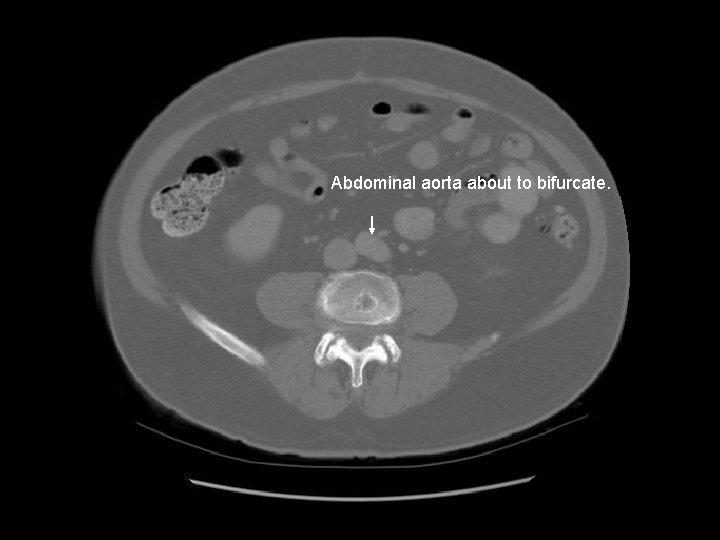

Abdominal aorta about to bifurcate.

Psoas

Rt common iliac artery IVC Lt common iliac artery

L 5